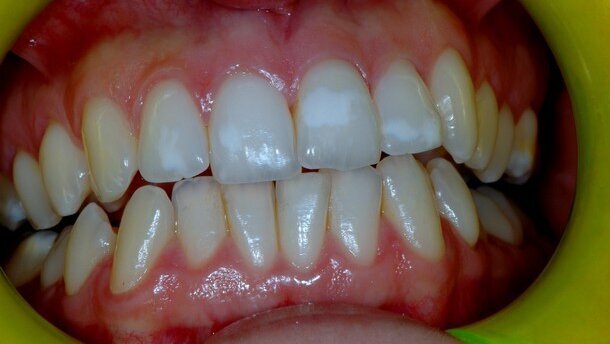

Se la malattia celiaca insorge durante lo sviluppo dei denti permanenti, (prima dei 7 anni), si possono verificare anomalie nella struttura dello smalto(9). La letteratura sostiene che tali difetti sono prevalenti nella dentizione mista/permanente (9,5%-95,9%; media 51,1%) rispetto alla decidua (5,88%-13,3; media 9,60%)(10). Questo dato si spiega considerando che lo sviluppo delle corone dei denti permanenti si verifica tra i primi mesi di vita e il settimo anno (dopo l’introduzione del glutine), mentre la formazione dei denti decidui avviene principalmente a livello uterino. Tuttavia, la presenza di difetti dello smalto anche in dentizione decidua supporta l’ipotesi che fattori immuno-genetici siano coinvolti nello sviluppo delle anomalie dentarie correlate alla celiachia. Aine ha classificato l’ipoplasia dello smalto dei celiaci in quattro gradi (Tab. 1). L’ipoplasia di grado I e II sono di più comune osservazione.

Questi difetti hanno una disposizione cronologica, ossia la noxa patogena ha agito nello stesso periodo, determinando delle lesioni che sono tutte alla stessa altezza delle superfici dentali. Tali lesioni sono inoltre distribuite in maniera simmetrica nei quattro quadranti (Fig. 1).

Gli incisivi sono i denti più colpiti, seguiti dai molari, canini e premolari(11). Tale differente distribuzione sembra essere correlata allo sviluppo cronologico della dentizione permanente, essendo gli incisivi e i primi molari i primi denti a calcificare. Il minor coinvolgimento dei denti che calcificano successivamente potrebbe essere spiegato considerando che il loro processo di calcificazione inizia quando la malattia celiaca dovrebbe essere già stata diagnosticata e quindi il glutine eliminato dalla dieta(12).